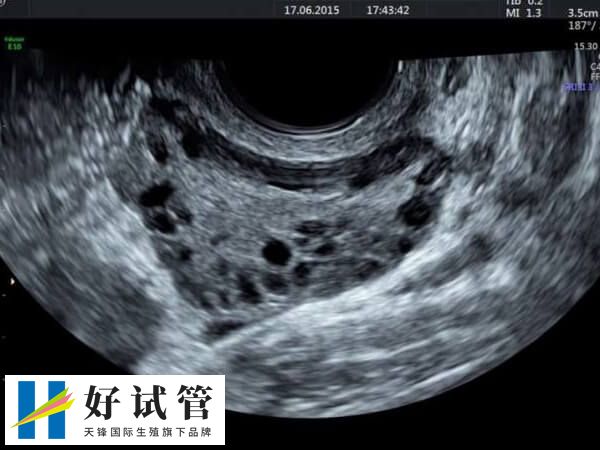

1、多囊卵巢综合征

多囊卵巢综合征是一种常见的内分泌失调疾病,其特点是卵巢不断形成多个小囊肿,导致排卵障碍。由于试管微刺激方案可以促进卵泡的发育和成熟,因此适合PCOS患者使用。